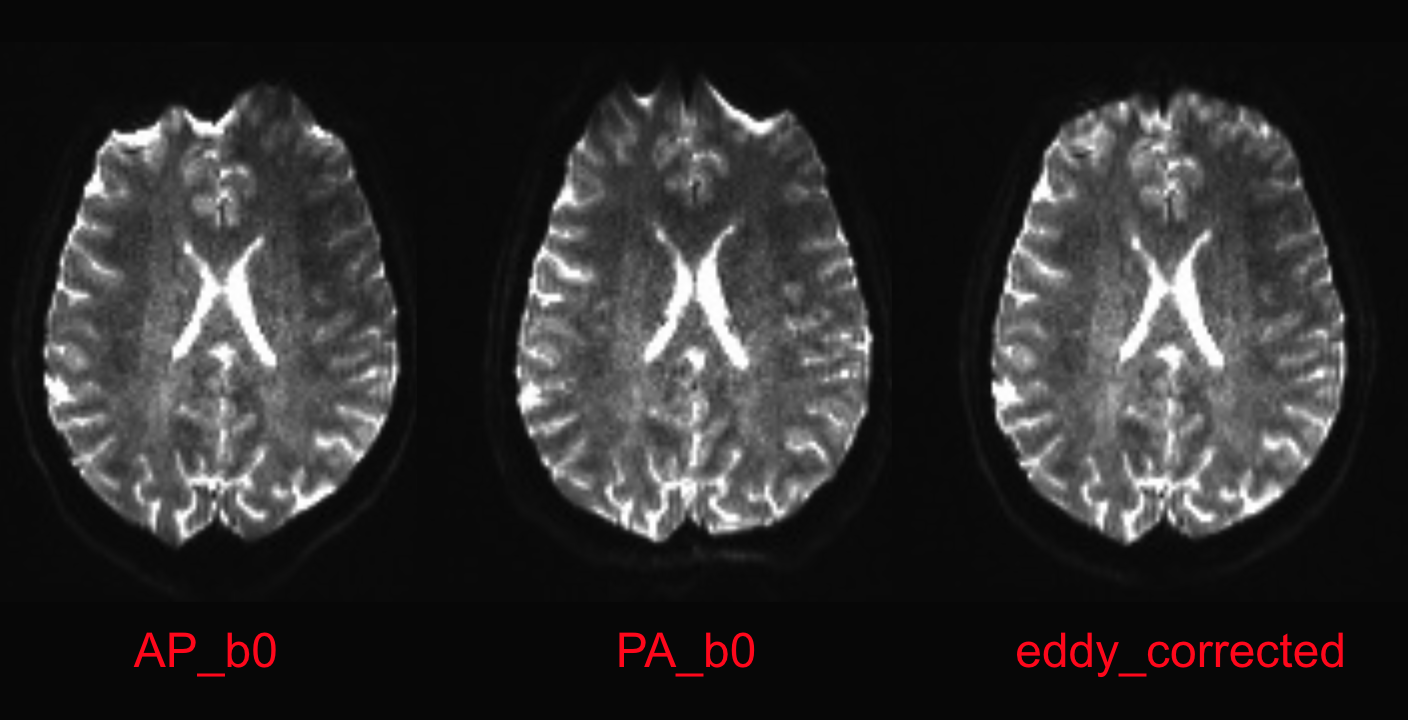

The first 8 volumes of each demodat DWI run are b0 images. We will extract the first volume of both runs using the command fslroi, and merge them over time using fslmerge. The result of these transformations is one image named AP_PA_b0, which contains 2 b0 volumes: one in each PE direction.

fslroi sub-101_ses-01_acq-b1500_dir-ap_dwi.nii.gz AP_b0.nii.gz 0 1 \

fslroi sub-101_ses-01_acq-b1500_dir-pa_dwi.nii.gz PA_b0.nii.gz 0 1 \

fslmerge -t AP_PA_b0 AP_b0.nii.gz PA_b0.nii.gz